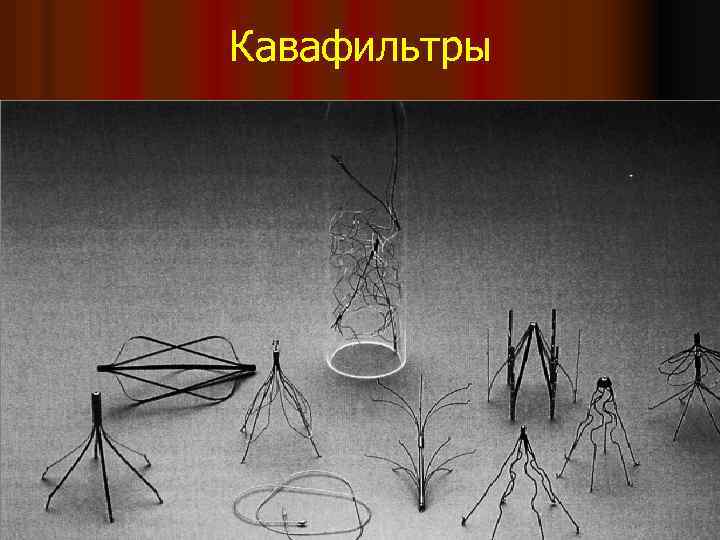

Кавафильтры